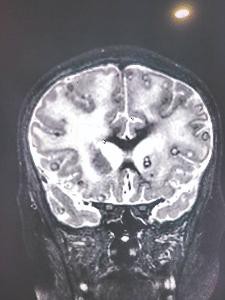

醫生決定為她再次進行腦掃瞄,才發現她是患上腦囊蟲病(Neurocysticercosis),腦部竟然有100顆絛蟲(Tapeworm)的蟲卵,處方解充血藥(decongestants)、類固醇和驅蟲劑,逐漸康復,可再次走路和上學。